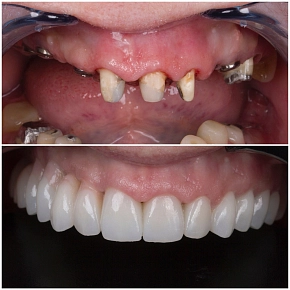

Красивая улыбка наших пациентов – залог успеха!